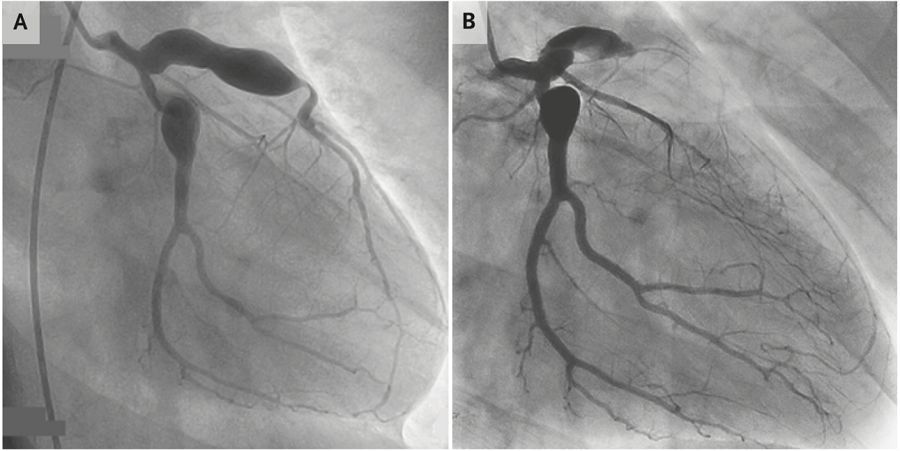

但这样的想法只持续了几分钟,因为患者的心电图清楚地显示,V1-V4导联ST段抬高(图1),似乎在和所有人较真“怎么的,老子就是心肌梗死”。再NB的概率也抵不过活生生的ST段抬高啊,于是只能乖乖地给患者安排冠脉造影,让人意外的是,“勉强的冠脉造影”提示前降支闭塞(图2)。什么鬼?真的18岁得了心肌梗死!

图2 冠脉造影提示多发瘤样扩张,前降支近端闭塞

仔细去看患者冠脉造影的结果,除了前降支的闭塞外,还存在着多发的瘤样扩张。毕竟是18岁的心肌梗死,必然有其特殊原因,于是重新仔细采集患者的病史:有没有经常熬夜?有没有高血压?有没有糖尿病?有没有家族性高胆固醇血症?答案统统是否定的。